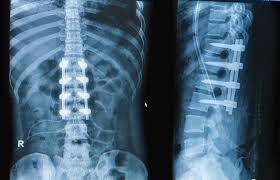

The Spine Surgery Department specializes in the diagnosis, treatment, and surgical management of disorders affecting the spine, neck, and back. Our expert spine surgeons provide comprehensive care for patients suffering from spinal injuries, deformities, degenerative conditions, infections, and tumors.

• Spinal deformity correction (scoliosis, kyphosis)

• Spine trauma and fracture management